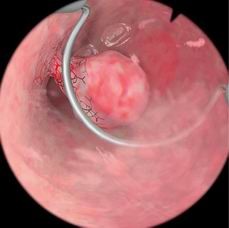

Essure植入体避孕模块

用于培训学员练习如何安置永久性节育装置